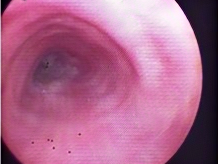

患者王先生(化名),因长期咳嗽、胸闷、气促前往我院呼吸与危重症医学科就诊,查胸部CT后,见到左主支气管下端完全阻塞,并伴有胸腔积液,考虑肺癌;随后呼吸与危重症医学科专家团队为患者实施经支气管镜检查,发现患者左主支气管壁存在肿瘤组织,病理报告显示肺鳞癌,最终在科室专家严格的诊断下,确诊为:左肺鳞癌IIIB期(中晚期)。

考虑患者自身情况,经科室专家团队严谨的讨论评估,若进行外科手术将切除全肺,患者生活质量将大幅下降,在充分征求患者及家属意见并同意后,科室为患者制定了放射性粒子植入治疗的方案并实施治疗。治疗三周后,复查支气管镜,患者左支气管通畅,治疗一月后,病灶稳定并呈现缩小的趋势。